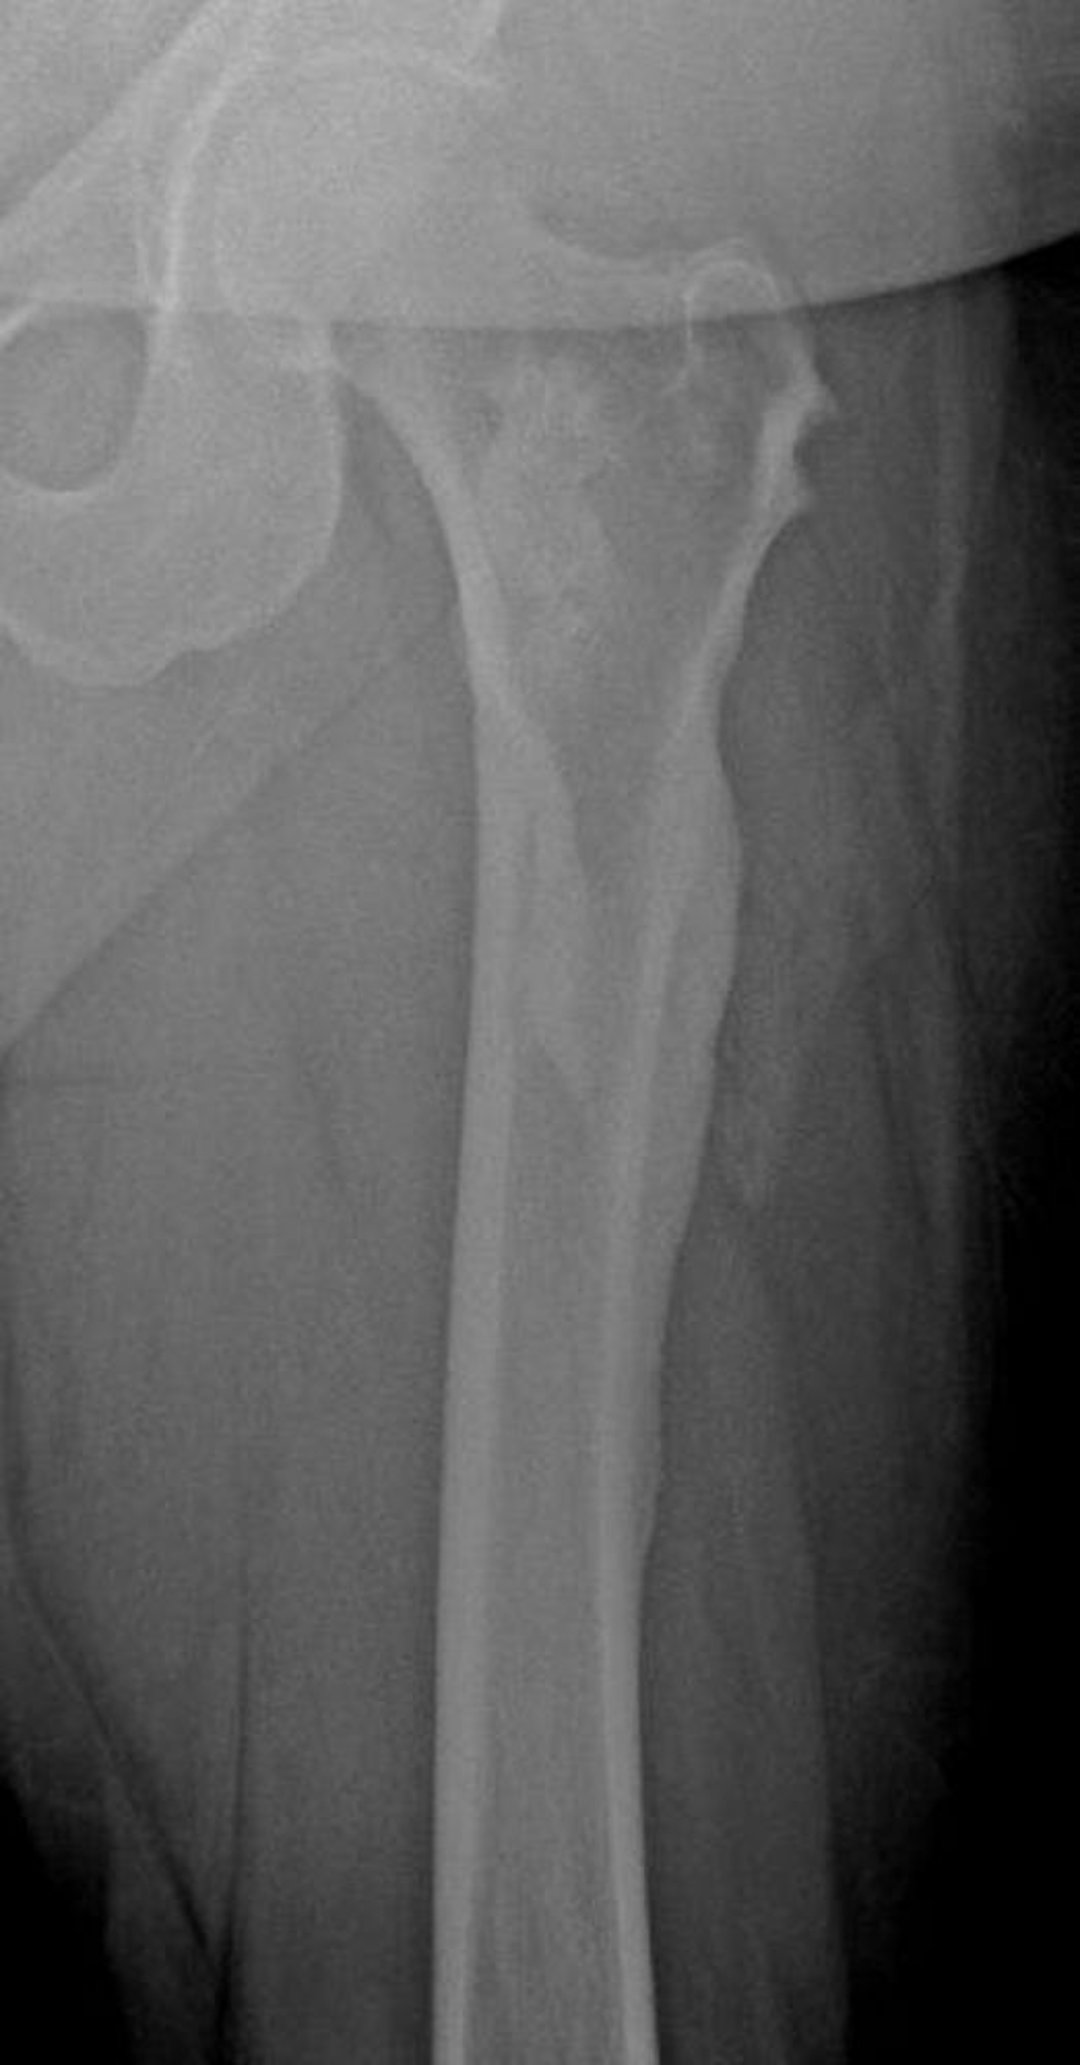

Meloreostosi (cera di candela che gocciola)

Questa RX mostra l'aspetto di "cera di candela gocciolante" della meloreostosi nel femore; è particolarmente evidente a livello della corticale femorale laterale.